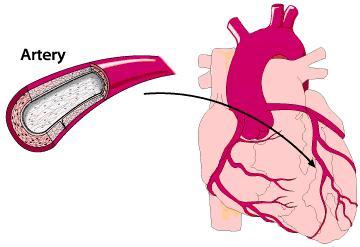

什么是心梗

心梗,即心肌梗死。

简单说,心脏是一个血泵,像抽水机一样日夜工作,将血液输送到身体各个部位。而心脏上的冠状动脉(血管)相当于抽水机的供电电线,是给这个泵供血的。冠状动脉闭塞,就好比电线不能正常传电,血泵就断电,不工作了,就是心梗了。

心脏停止工作后,因为没有血压,血液不流动,不能给机体带来新鲜氧气,身体的细胞就死了,那意味着整个人已经陷入危险境地了。